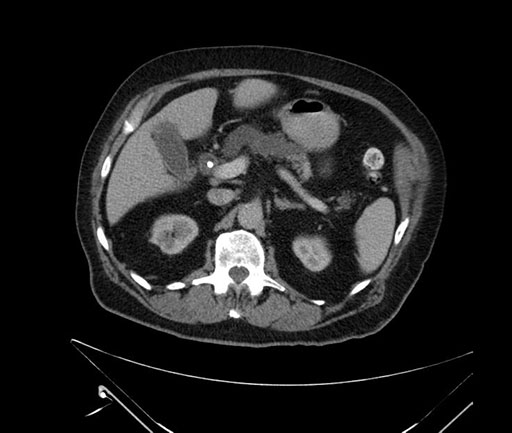

Imaging Analysis

Look through the patient's CT scan to identify any areas of concern for the necessary procedure.

Based on your CT findings, which issue(s) would give reason for "planned slowing down moment(s)" in this case?

Considering a standard Whipple procedure, what step(s) of the operation would you do differently in this case?